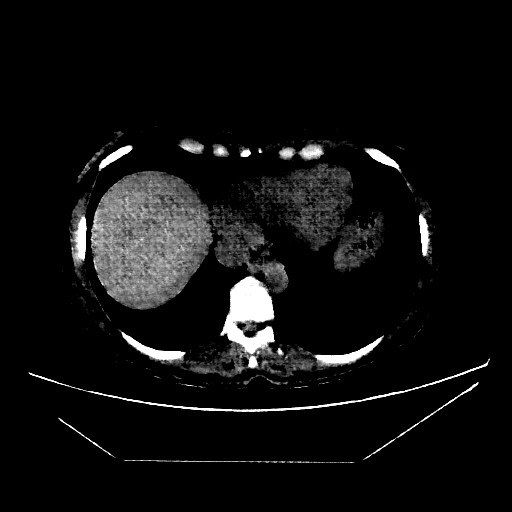

Generated VENOUS CT scan (A→B translation)

No window - Raw intensity values

Lung window (WL -600, WW 1500 β†’ Low βˆ’1350, High +150)

Mediastinum window (WL 40, WW 400 β†’ Low βˆ’160, High +240)